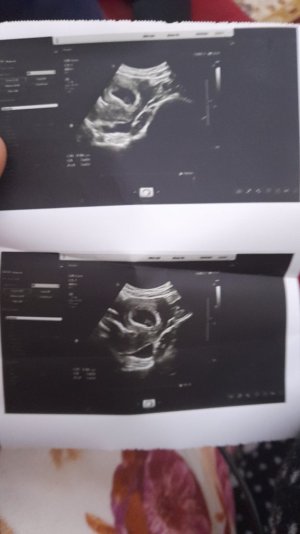

NUB TEORİSİNE GÖRE CİNSİYET TAHMİNİ

Nuba göre kız gibi geldi12+6 haftalığız nub teorsine cinsiyet tahmininde bulunur musunuz??

Bana erkek gibi geldi12+6 haftalığız nub teorsine cinsiyet tahmininde bulunur musunuz??

kız diyorum12+6 haftalığız nub teorsine cinsiyet tahmininde bulunur musunuz??

Yanlış yazmışım 12+3Doktor hiçbişey söylemedi bize de tahminde bulunurmusunuz ? 7+3

Kız tabikide %10012+6 haftalığız nub teorsine cinsiyet tahmininde bulunur musunuz??

banada bakarmisiniz 7 haftalik karindan ultrason kalp atisi 160 iki prenses im var erkek istiyorum en onemlisi saglikli hayirli evlat olsun tabiki gonul olmayani istiyorNuba göre kız :)